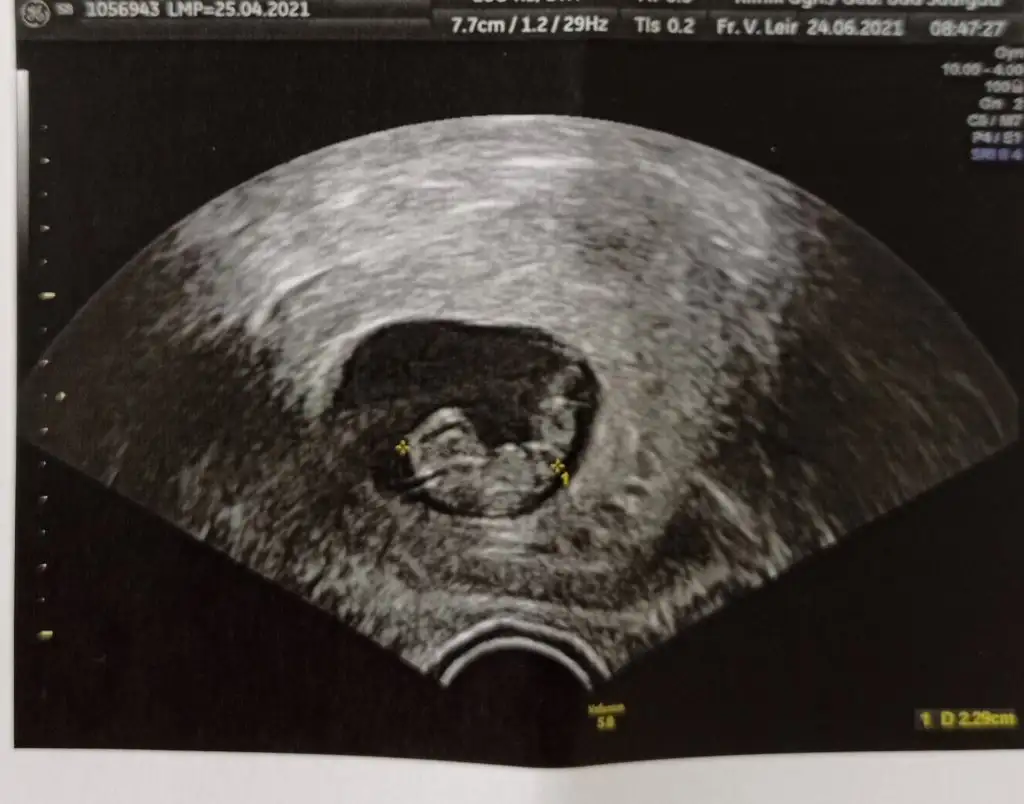

Ya çok güzel bir sayfa🤗 Benimkini de yorumlar mısınız kızlar ? Vajinal ultrason ikisi de. Haftaları yazıyor resme tıklayınca.

Eklentiler

• 7+3.webp

7+3.webp

30,9 KB · Görüntüleme: 74

• 8+3.webp

8+3.webp

28 KB · Görüntüleme: 88